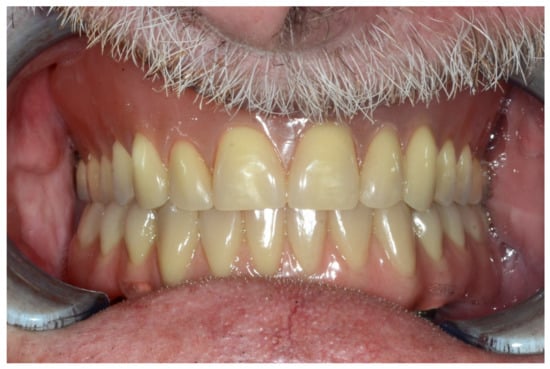

A screw-retained provisional fixed prosthesis was used for 4 months to condition peri-implant mucosa, and in October 2013, the final prosthesis was installed. The occlusion was adjusted, and the patient received instruction for oral hygiene. A follow-up assessment at 8 years showed a stable cosmetic, biological and functional reconstruction (Figure 27, Figure 28 and Figure 29).

Figure 27.

Resting frontal close-up views.

Figure 28.

Smile frontal close-up views.